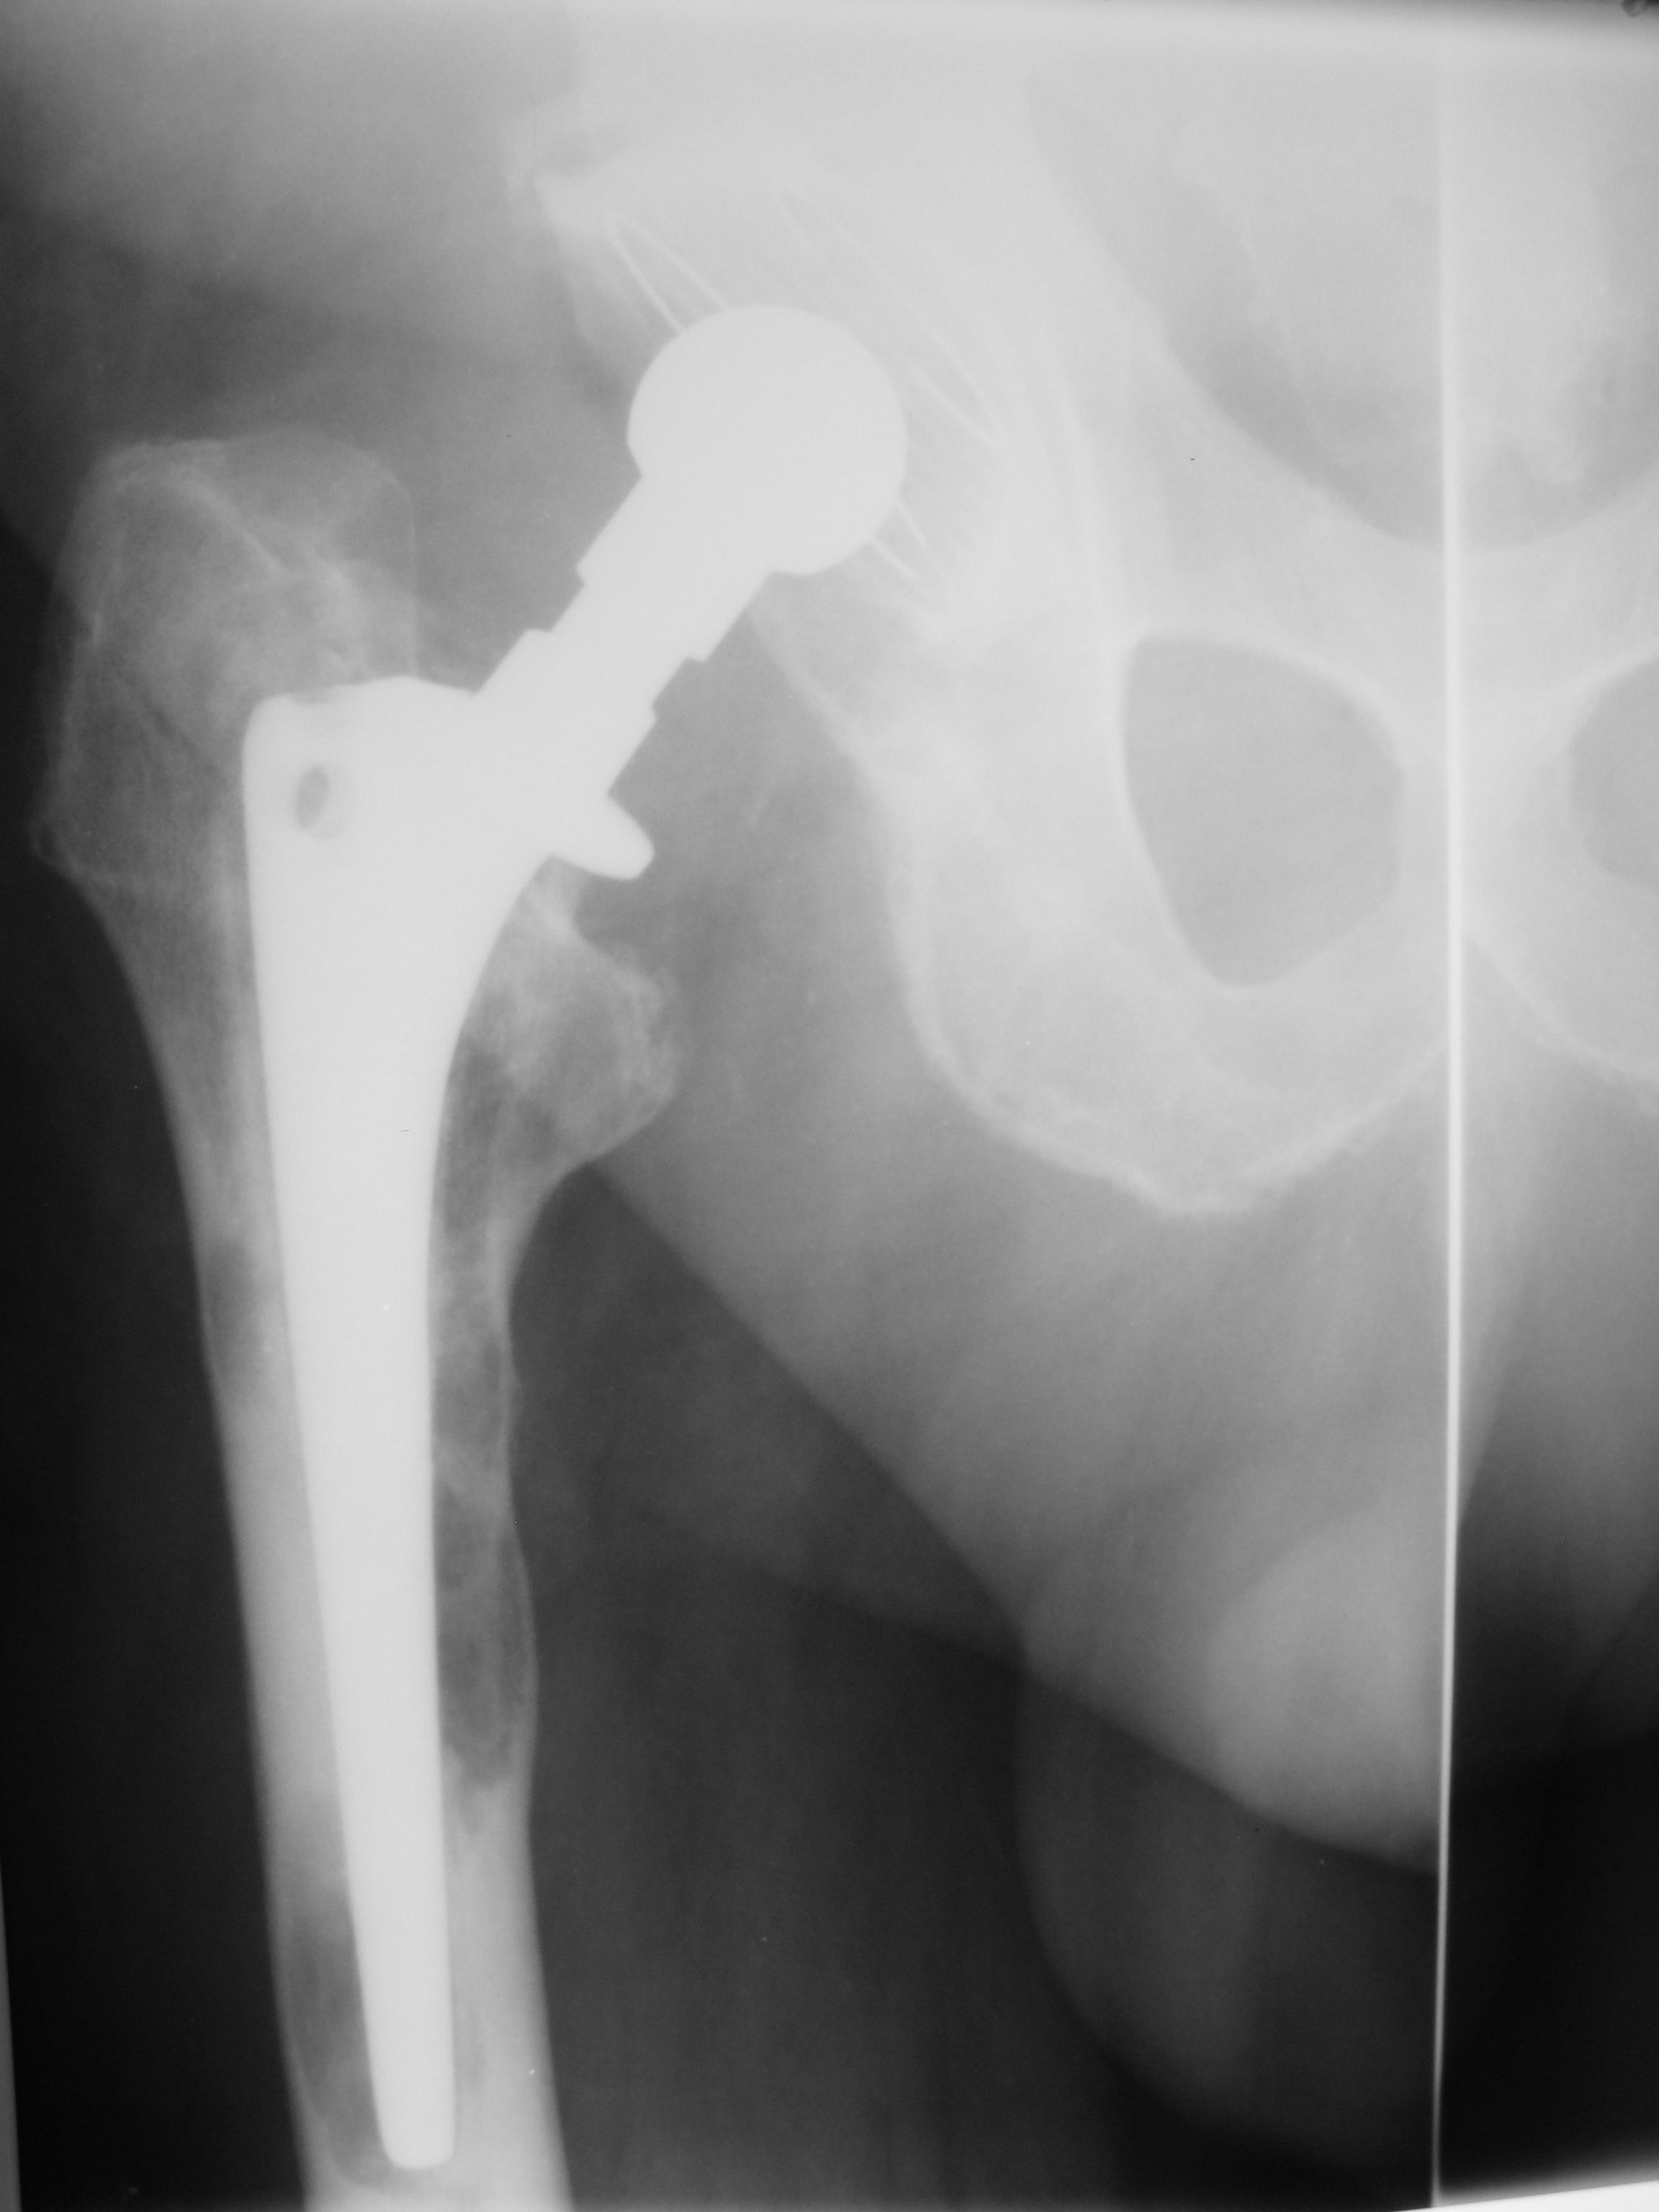

Пациент около 70 лет, эндопротезирование в 2000 г, несколько недель назад появились боли в правом т\б суставе, передвигается на костылях. Смущает вздутие кости на границе 6 и 5 зоны https://radiomed.ru/sites/default/files/styles/case_slider_image/public/user/18954/img_2790.jpg?itok=XxLCW49E ID:46947 Пнд, 07/04/2014 - 22:41 #1 И.Бондаренко Не на сайте Был на сайте: 2 дня 5 часов назад Зарегистрирован: 13.09.2011 - 22:55 Публикации: 9206 Сделайте всё бедро Пнд, 07/04/2014 - 23:43 #2 JJ Не на сайте Был на сайте: 11 лет 5 месяцев назад Зарегистрирован: 03.04.2014 - 20:35 Публикации: 102 И.Бондаренко wrote: Сделайте всё бедро согласна, необходим снимок всего бедра Втр, 08/04/2014 - 01:07 #3 Андрей Юрьевич Не на сайте Был на сайте: 1 неделя 3 дня назад Зарегистрирован: 16.11.2008 - 22:16 Публикации: 18098 Смущает - отметьте. А для полноценного заключения надо смотреть предыдущий вснимок. Андрей Юрьевич Втр, 08/04/2014 - 09:34 #4 schlyapa Не на сайте Был на сайте: 8 лет 2 недели назад Зарегистрирован: 27.09.2013 - 22:15 Публикации: 613 Последний снимок в 2008 г в больнице, по выписке - без патологии. Картина не типична для резорбции? Втр, 08/04/2014 - 10:53 #5 Сан Саныч1 Не на сайте Был на сайте: 11 месяцев 3 недели назад Зарегистрирован: 07.06.2010 - 21:17 Публикации: 2114 Это не резорбция, при ней вздутия не бывает. Это агрессивный гранулематоз(цементная болезнь, в оригинале - particle desease). По своей сути - имунная (аллергическая) реакция на компоненты материала протеза/чашки/цемента. http://www.learningradiology.com/archives2010/COW%20431-Particle%20disease/particlecorrect.htm Хочешь сделать что-то нормально - сделай это сам! Втр, 08/04/2014 - 13:16 #6 арнольд Не на сайте Был на сайте: 2 года 1 день назад Зарегистрирован: 22.12.2008 - 16:50 Публикации: 196 Топикстартеру: можно по-подробнее о нумерации зон? Я этого не знаю!! Dat.Dicat.Dedicat. Втр, 08/04/2014 - 13:24 #7 svetlana292929 Не на сайте Был на сайте: 3 года 8 месяцев назад Зарегистрирован: 18.06.2012 - 13:53 Публикации: 869 Арнольд, полистайте Приложения: ВложениеРазмер endoprotezirovanies.pdf1.13 МБ Втр, 08/04/2014 - 16:10 #8 NIL Не на сайте Был на сайте: 4 дня 7 часов назад Зарегистрирован: 25.11.2013 - 20:50 Публикации: 18206 Сан Саныч1 wrote: Это не резорбция, при ней вздутия не бывает. Это агрессивный гранулематоз(цементная болезнь, в оригинале - particle desease). По своей сути - имунная (аллергическая) реакция на компоненты материала протеза/чашки/цемента. http://www.learningradiology.com/archives2010/COW%20431-Particle%20disease/particlecorrect.htm Спасибо! Просветили "Слушай всех, прислушивайся к немногим, решай сам".© Втр, 08/04/2014 - 16:14 #9 atexta Не на сайте Был на сайте: 2 года 10 месяцев назад Зарегистрирован: 08.02.2014 - 18:41 Публикации: 4842 Сан Саныч1 wrote: Это не резорбция, при ней вздутия не бывает. Это агрессивный гранулематоз(цементная болезнь, в оригинале - particle desease). По своей сути - имунная (аллергическая) реакция на компоненты материала протеза/чашки/цемента. http://www.learningradiology.com/archives2010/COW%20431-Particle%20disease/particlecorrect.htm Спасибо, столько протезов сейчас, а такого не видела , а как с такими пациентами дальше поступают ? Не нам судить… Чт, 10/04/2014 - 20:51 #10 schlyapa Не на сайте Был на сайте: 8 лет 2 недели назад Зарегистрирован: 27.09.2013 - 22:15 Публикации: 613 Досняли бедро, ниже протеза изменений нет.

Последний снимок в 2008 г в больнице, по выписке - без патологии. Картина не типична для резорбции?

Это не резорбция, при ней вздутия не бывает. Это агрессивный гранулематоз(цементная болезнь, в оригинале - particle desease).

По своей сути - имунная (аллергическая) реакция на компоненты материала протеза/чашки/цемента.

Досняли бедро, ниже протеза изменений нет.